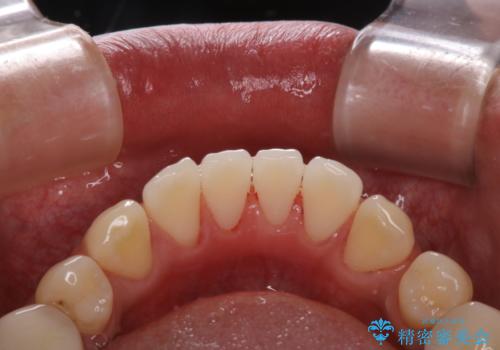

虫歯治療を始める前のPMTC